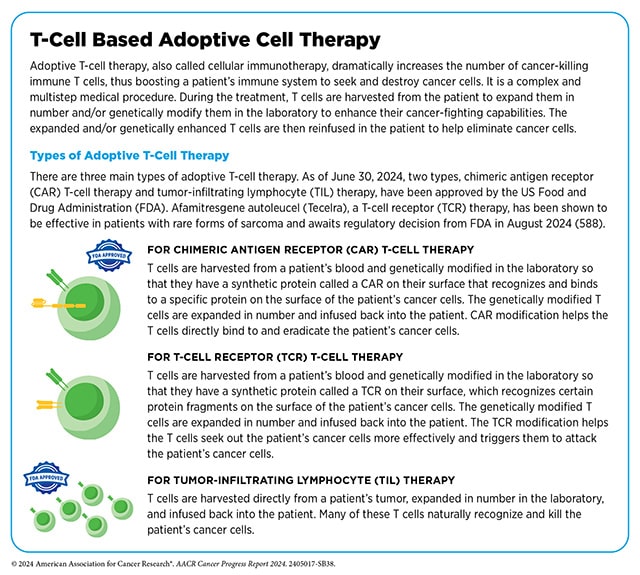

The first was a type of cellular immunotherapy called a T-cell receptor (TCR) T-cell therapy. Like chimeric antigen receptor (CAR) T cells, TCR T cells are made by harvesting T cells from the blood of cancer patients, engineering them in the lab to target cancer cells, and infusing them back into patients to fight cancer.

Unlike CAR T cells, TCR T cells are engineered to express a modified version of the naturally occurring T-cell receptor instead of a chimeric receptor. TCR T cells recognize tumor antigens presented by proteins called human leukocyte antigens (HLAs) whereas CAR T cells directly bind to target proteins on the surface of cancer cells.

- Afamitresgene autoleucel (Tecelra; afami-cel) is the first TCR T-cell therapy approved for use in cancer. It received accelerated approval this quarter for the treatment of certain adult patients with unresectable or metastatic synovial cell sarcoma, a type of soft tissue sarcoma, who have received prior chemotherapy.

Afami-cel is designed to recognize fragments of the protein MAGE-A4, which is expressed in some synovial cell sarcomas. It also recognizes the HLA proteins that present these fragments; because each individual has a different fingerprint of HLA types, afami-cel is approved to treat patients with MAGE-A4-positive tumors who test positive for an HLA recognized by afami-cel.